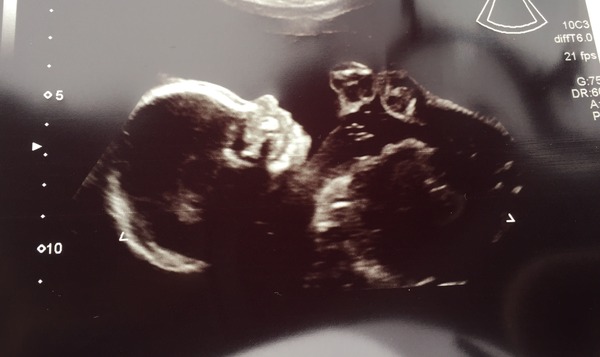

Dileas29 · 24/03/2016 21:13

lil glad procedure went well, what a fright you must've got, you will be exhausted. Lots of rest for you.

Scan today and all went smoothly, 40 minutes of seeing Baby as sonogram woman had a trainee in so they spent lots of time going over everything in detail which was great! This also meant I had to go to the toilet and do star jumps on two occasions to get the baby into positions they were looking for.

We found out what flavour too, baby GIRL on the way!! Delighted as our loft full of girl clothes will go to good use!